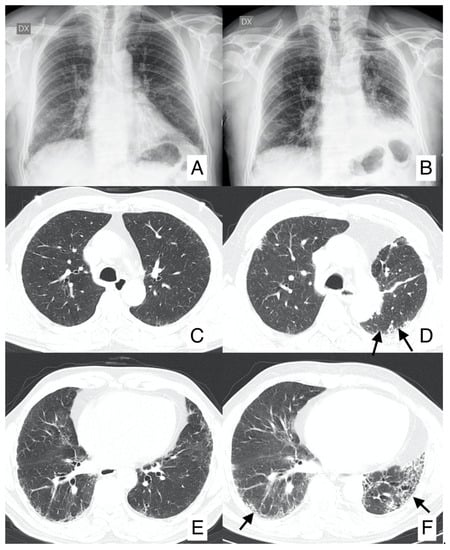

4.2. Acute Exacerbation